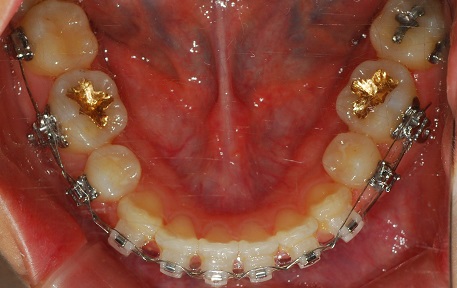

상악 사진

하악사진

왼쪽 끝에 와이어 끊어 놓은거 보이시죠?

(거울로 찍어서 왼. 오른쪽이 바뀌어서 보임)